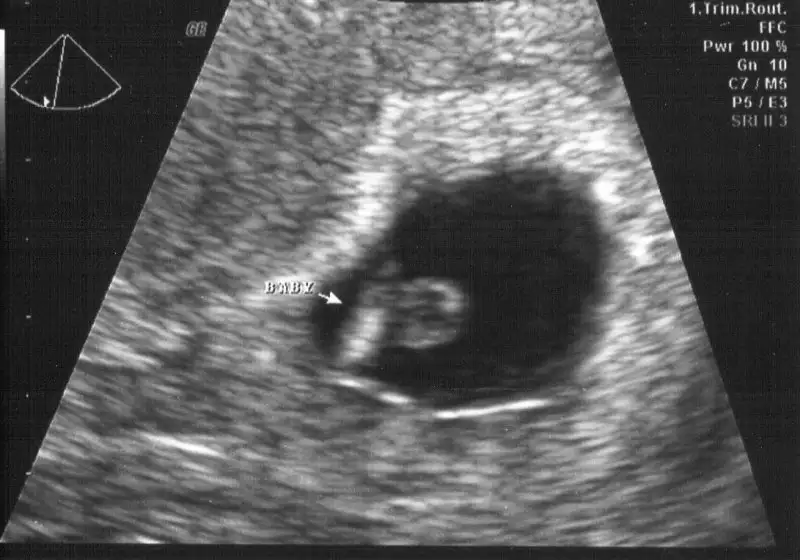

Kız gibi cnm bebek sağda,usg karından mi.

Evet canim karindan. Insallah hayilisiylaKız gibi cnm bebek sağda,usg karından mi.

Cnm sen 20 haftalık oldun ve daha öğrenemedin mi. Daha öncede söylediğim gibi plasentan sağda bu teoride kız olabilir. Fakat bebeğin büyümüş canım artık sürekli yer değiştirir bi solda bi sağda olur. Bu resimde bebek solda plasentan sağda. Senin ikiside yanyana olur teorin bu görüntüyle çürümüş oldu cnm. Plasentan eski usg resimlerinde de sağda. Eğer sağ kız demekse senin kızın olcak.oğlun olursa burdaki konuyu kapatalım tüm bu teorilerin yalan olduğuna inanalımm